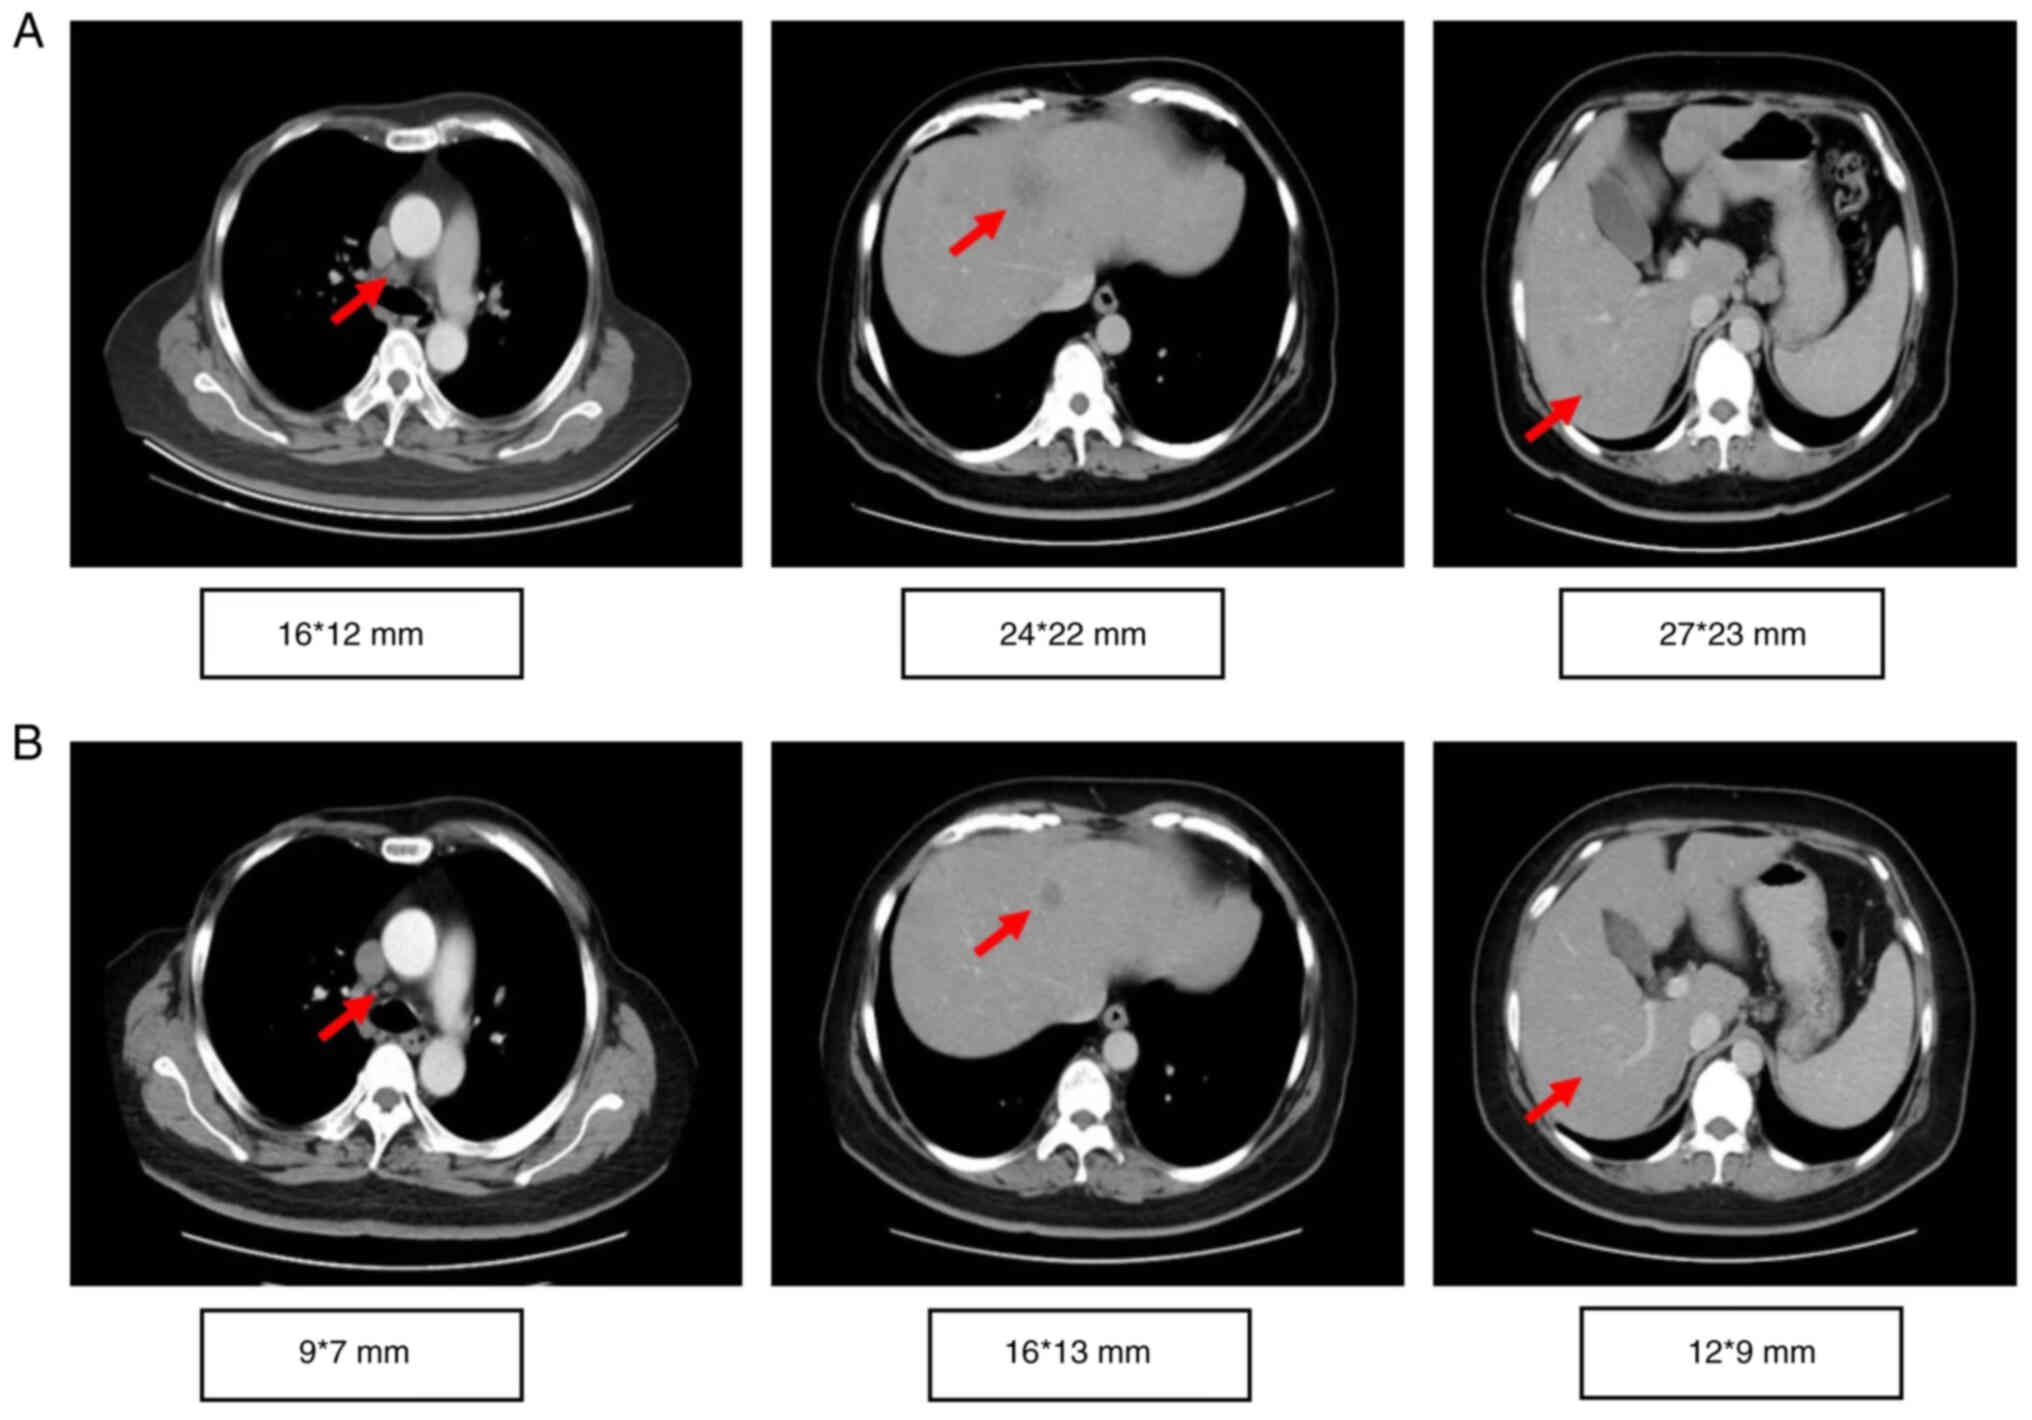

The proband, a 56-year-old woman, underwent a modified radical mastectomy for left breast cancer in May 2004. The pathological diagnosis was medullary carcinoma, pT2N0M0, stage IIA, estrogen receptor (ER)−, progesterone receptor (PR)− and human epidermal growth factor receptor (HER2)1+. The patient received four cycles of adriamycin/cyclophosphamide (dose unknown) regimen. Right breast cancer was diagnosed during the routine follow-up examination and a modified radical mastectomy was performed in May 2016. The pathological diagnosis was invasive ductal carcinoma, pT1N2M0, stage IIIA, ER+++, PR−, HER21+ and Ki-67 (30%). Germline or somatic mutations were not identified at this time. Based on clinical pathology, chemotherapy with epirubicin (90 mg/m2)/cyclophosphamide (600 mg/m2) for four cycles with weekly paclitaxel (80 mg/m2) for 12 weeks was performed from August 2016 to July 2017, followed by 5,000 cGy/25f radiotherapy targeting the chest wall and supraclavicular region. Letrozole (2.5 mg QD) was administered until multiple tumor metastases were detected in bone, liver and lymph nodes (left cervical lymph nodes, clavicular area and internal mammary, right hilar lymph nodes and mediastinal, lung and liver hilar and retroperitoneal lymph nodes) by PET/CT in October 2018. The proband refused biopsy of the metastatic sites. The proband had multiple liver metastases with a maximum metastatic focus 3.1×2.6 cm. The tumor burden was high with multiple liver, lymph node and bone metastases. Due to primary adjuvant endocrine resistance and palbociclib, the only available CDK4/6 inhibitor in China at that time (October 2018), was not affordable for the patient, the patient received combination chemotherapy. Chemotherapy with abraxane (125 mg/m2 d1,d8 q21d) combined with capecitabine (1 g/m2 d1-14 q21d) was initiated but the disease continued to progress in the liver after two cycles (Fig. 1). The timeline of her past medical history is outlined in Table I. The patient had a family history of breast and ovarian cancer (Fig. 2). Targeted next-generation sequencing testing with a panel of 18 cancer genetic susceptibility genes was performed. Genomic DNA (gDNA) was extracted from paraffin-embedded section of the primary tumor with AllPrep DNA/RNA mini Kit (Qiagen 80204). The libraries of gDNA were constructed with a KAPA Hyper Prep kit (Kapa Biosystems, USA) according to the operation manual. gDNA libraries were enriched through a panel of 18 cancer genetic susceptibility genes with its custom-designed capture probes were manufactured by Agilent, USA. P5/P7 primers were adopted to amplify the enriched gDNA libraries. The amplified libraries were qualified by the 2200 Bioanalyzer (Agilent Technologies, Palo Alto, Calif) and quantified by the qBittorrent (version 3). Paired-end sequencing with reads length of 250 bp on the Hiseq X Ten platform (Illumina, San Diego, CA) using MiSeq Reagent Kit v3 (MS-102-3001, Illumina, USA) and the loading concentration was 4 pM. The NGS raw data was initially analyzed with trimmomatic-0.36. Reads were then aligned against human reference genome (version GRCh37/hg19) with bwa (version 0.7.10). Candidate somatic mutations were determined using Samtools (version 1.3.1) and pindel (version 0.2.5b8). Finally, filter alignment and sequencing artifacts were conducted using IGV (Integrative Genomics Viewer). Double deleterious germline mutations in both BRCA1 (S405X) and BRCA2 (W2990X) were identified (Fig. 3). On the basis of these mutations, the proband started olaparib treatment (600 mg BID) in January 2019. The most severe adverse event was anemia (grade 3), which occurred 4 months after the start of the treatment. Other side effects, including leukopenia, thrombocytopenia, loss of appetite and nausea were mild and well tolerated. To alleviate symptoms of anemia, olaparib treatment was suspended and the proband received erythropoietin (10,000 IU 3 times/week) and ferrous succinate tablets (0.1 g 3 times/day). Olaparib treatment was resumed at a decreased dosage (450 mg/day) when anemia was reduced to grade 2 after 1 week of the treatment. Grade 3 anemia reoccurred after 2 weeks of decreased dosage olaparib, thus olaparib was suspended, and erythropoietin and ferrous succinate tablets at the aforementioned dosage were administered to relieve the anemia. Subsequently, olaparib treatment was resumed with further decreased dosage (300 mg/day). Grade 3 anemia reoccurred and olaparib treatment was terminated in July 2019. The olaparib treatment intermittently lasted for a total of 6 months and CT imaging showed a partial response (35% reduction; Fig. 1A and B). The proband did not receive chemotherapy or palbociclib because of persistent grade 3 anemia and the prohibitive cost of palbociclib. The proband received oral exemestane (25 mg qd). The patient continued treatment elsewhere and did not disclose her condition during a follow-up telephone conversation 3 months later.

Figure 1.

Computed tomography scan results before and after treatment. Computed tomography scan of the chest and abdomen (A) before initiation (December 2018) and (B) after 6 six months of olaparib therapy (June 2019). Arrows state metastatic lesions.